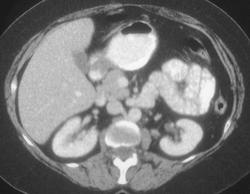

Gastric Ulcer in Adenocarcinoma